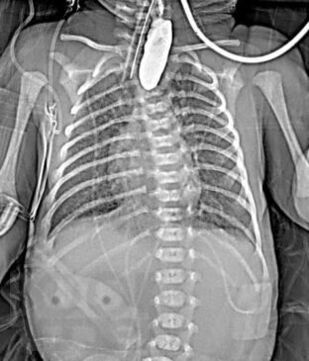

Диагностика и лечение хирургических заболеваний новорождённых и детей грудного возраста

В пособии рассматриваются современные принципы диагностики и лечения хирургических заболеваний новорождённых и детей первого года жизни, возможных осложнений и исходов. Акцентируем внимание студентов на эмбриогенез, этиологию и патогенез, классификацию, клинические проявления и выбор методов лечения. Пособие содержит вопросы для самоконтроля и список литературы для дополнительного изучения.